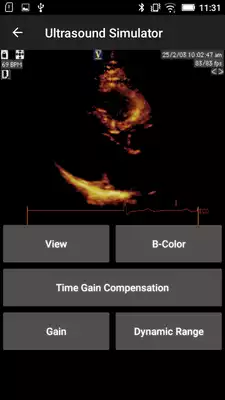

DESCRIPTION

Play this online game named Basic - Transthoracic Echocardiography.

This is the electronic course manual for registered participants of The Beyond BASIC - Transthoracic Echocardiography, The Chinese University of Hong Kong.Updates: